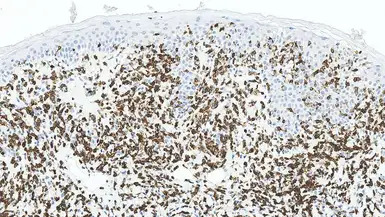

IHC-P analysis of human skin tissue with mycosis fungoides using GTX01936 CD3 antibody [LN10]. Note the extensively infiltrated positive cells.